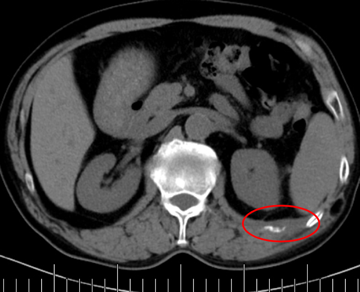

左側肋骨轉移

造影顯示紅圈內“烏云”區(qū)域為腫瘤。